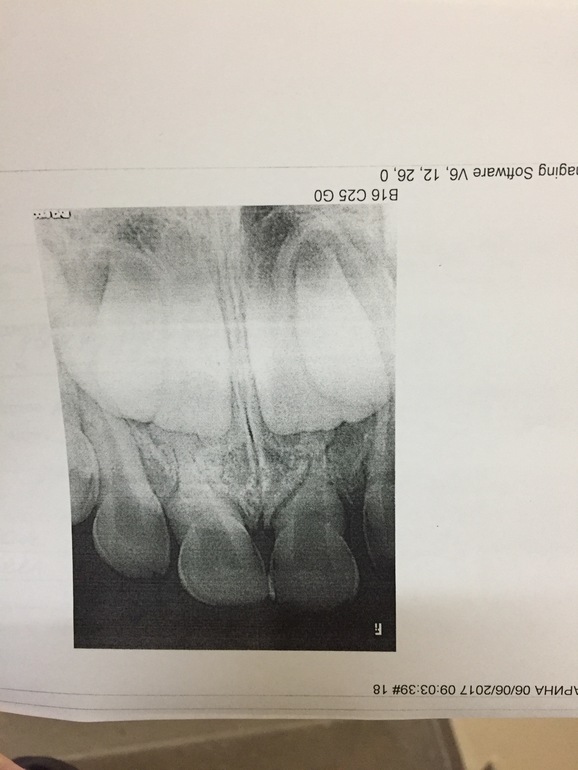

Здравствуйте, произошла такая ситуация дочь 5,5лет упала в игре с кровати, ударилась передними зубами. Шла сильно кровь ,появился отек качались прередние двойки .Что бы остановить кровь полоскали марганцовкой . На следующий день повезла ребёнка к врачу, настояла что бы сделали снимок ... стоматолог - хирурги выписала нам халисал, мирамистин для укрепления зубов 🤔 И сказала явится через 2 дня ! Мы пришли не чего мне не объяснила и выдернула зубы , после она сказав мне , что отек не сошёл зубы у вас не укрепились!😱